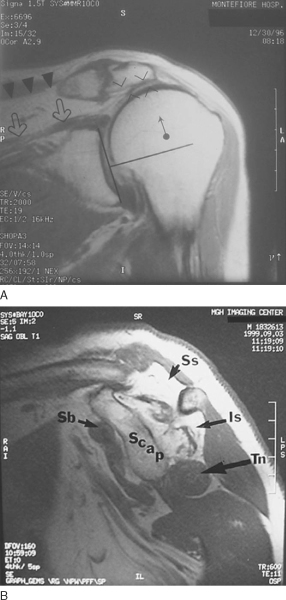

| • | Plain films may demonstrate static superior subluxation of the humeral head. An acromiohumeral distance of less than 7 mm (normal, 10.5 mm) suggests an irreparable tear of the infraspinatus ( Fig. 21-2A ). |

|

| • | Magnetic resonance imaging is performed to characterize the status of the rotator cuff tendons and to evaluate muscle atrophy and fatty infiltration. | |

| • | A massive tear, defined as a tear encompassing two or more tendons, with grade 3 or 4 fatty infiltration of the rotator cuff musculature on magnetic resonance imaging or computed tomography, portends a poor prognosis for a successful primary repair and as such is an indication for tendon transfer ( Fig. 21-2B ).[20] |

Figure 21-2 (B from Warner JJP. Management of massive irreparable rotator cuff tears: the role of tendon transfer. Instr Course Lect 2001;50:63-71.) |